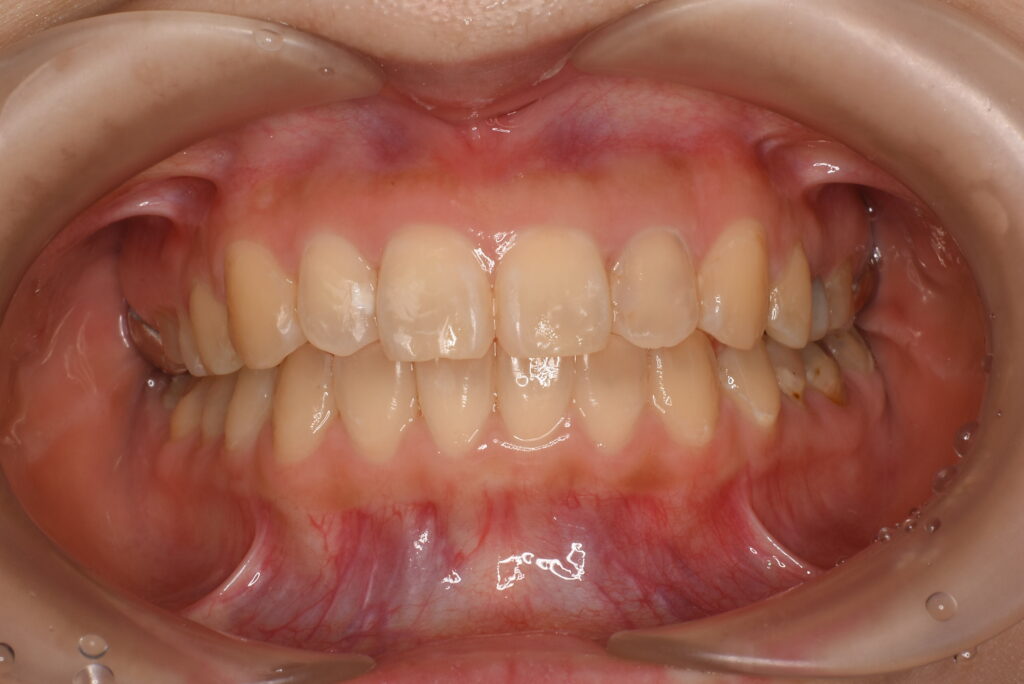

- BEFORE

| 治療内容 | 不揃いな歯並び(叢生)や、歯のガタガタ・デコボコが気になることを主訴に来院されました。 目立ちにくい装置での治療をご希望されたため、マウスピース型矯正(インビザライン)による矯正治療を行いました。 治療途中、上顎左右にカリエスが認められたため、矯正治療と並行してCR修復(コンポジットレジンによる虫歯治療)を行いました。 2021年12月にお引っ越しのご予定があり、2022年3月までの治療終了を希望されていたため、治療計画を調整しながら進行管理を行い、予定期間内での治療完了を目指しました。 |